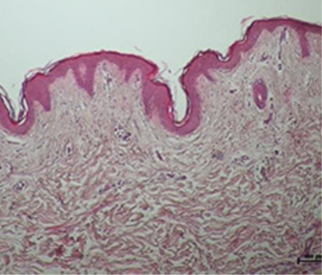

눈으로 직접 확인하는

콜라겐 활성 변화

온다리프팅 시술 후 진피의 콜라겐이 활성화 되고

늘어져 있던 콜라겐이 수축되는 것을 알 수 있습니다.

스킨타이트닝과 리프팅 효과가 동시에 이루어져

만족스러운 피부 리모델링이 이루어집니다.

*진피의 콜라겐(분홍색 영역) 활성화